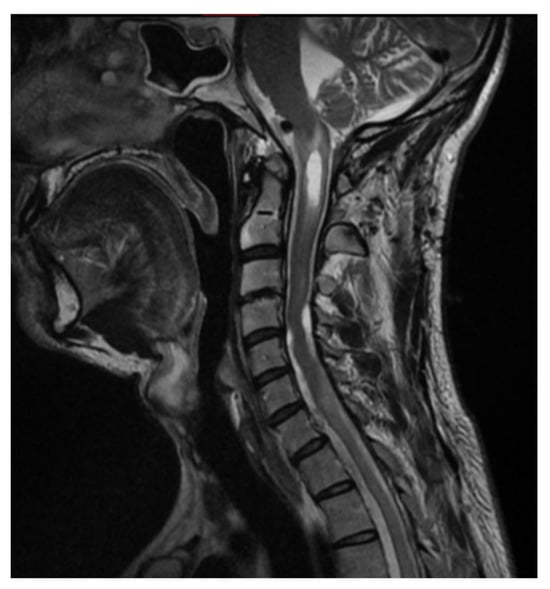

Case Report